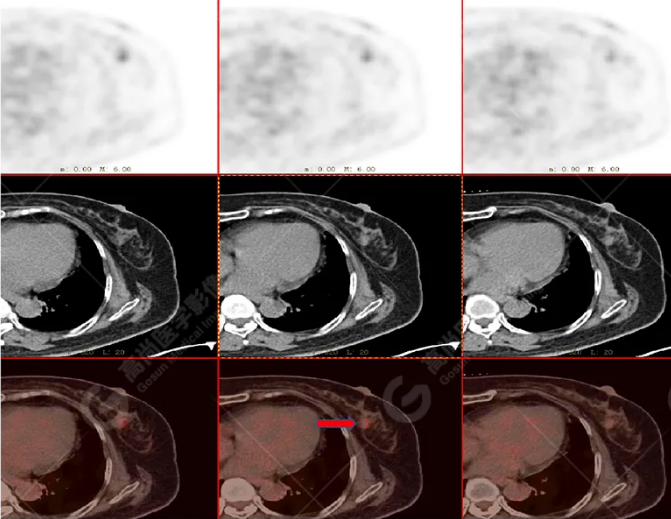

病史摘要:女性 36歲 因左后肋區(qū)疼痛1月余查體,無其他不適。PET/CT影像圖

左胸一后肋溶骨性骨質(zhì)破壞,周圍伴軟組織形成,F(xiàn)DG代謝增高,SUVmax為10.9。

找到引起骨痛病灶,病因:原發(fā)?轉(zhuǎn)移?感染?

最終診斷:宮頸癌伴肋骨單發(fā)骨轉(zhuǎn)移。